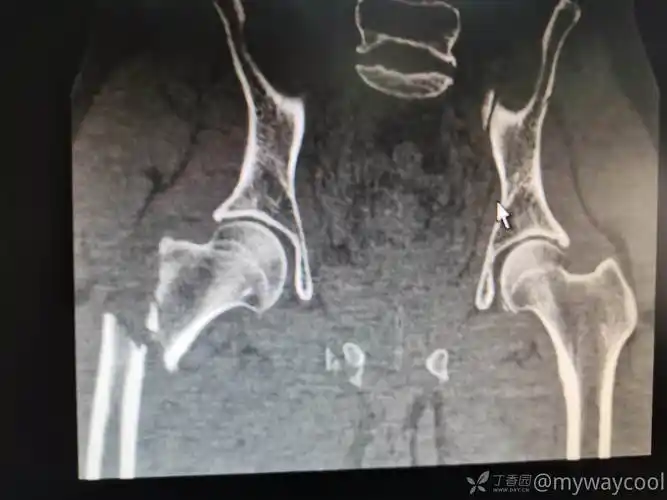

股骨近端粉碎骨折术前术后

一例股骨近端粉碎骨折

股骨近端粉碎骨折